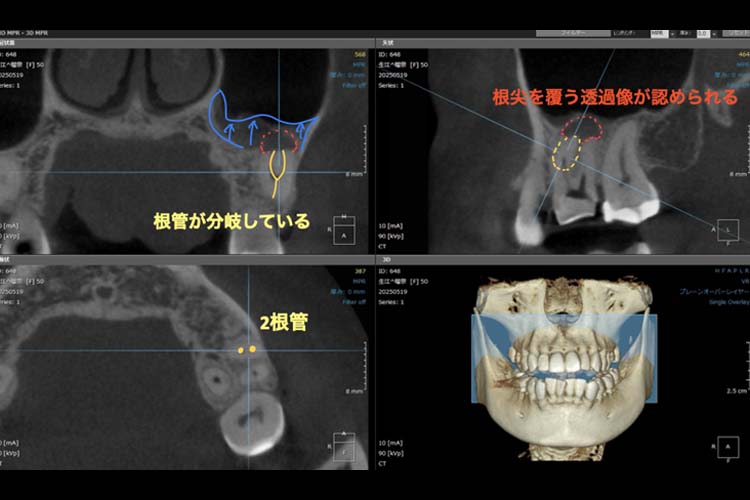

| 治療内容 | 左上6番近心頬側第二根管の見逃しによる再感染のため、マイクロスコープ下にて根管治療を行った。 |

- 古い材料や虫歯を取り切った上で、見逃している根管がないかマイクロスコープやCT撮影にて確認

- MB2(近心頬側第2根管)の存在を確認したため、拡大形成

MB2の見逃し、緊密に根管充填がなされていないことが再感染の原因と考えられます。

MB2を肉眼で見つけて治療することは困難な場合が多いため、マイクロスコープやCTを用いて根管治療を行うことが大切です。

MB2という小さな根管の発見率において裸眼では18.2%〜51%、ルーペでは41.3%ですが、マイクロスコープを用いると82%〜95.2%になると報告されています。